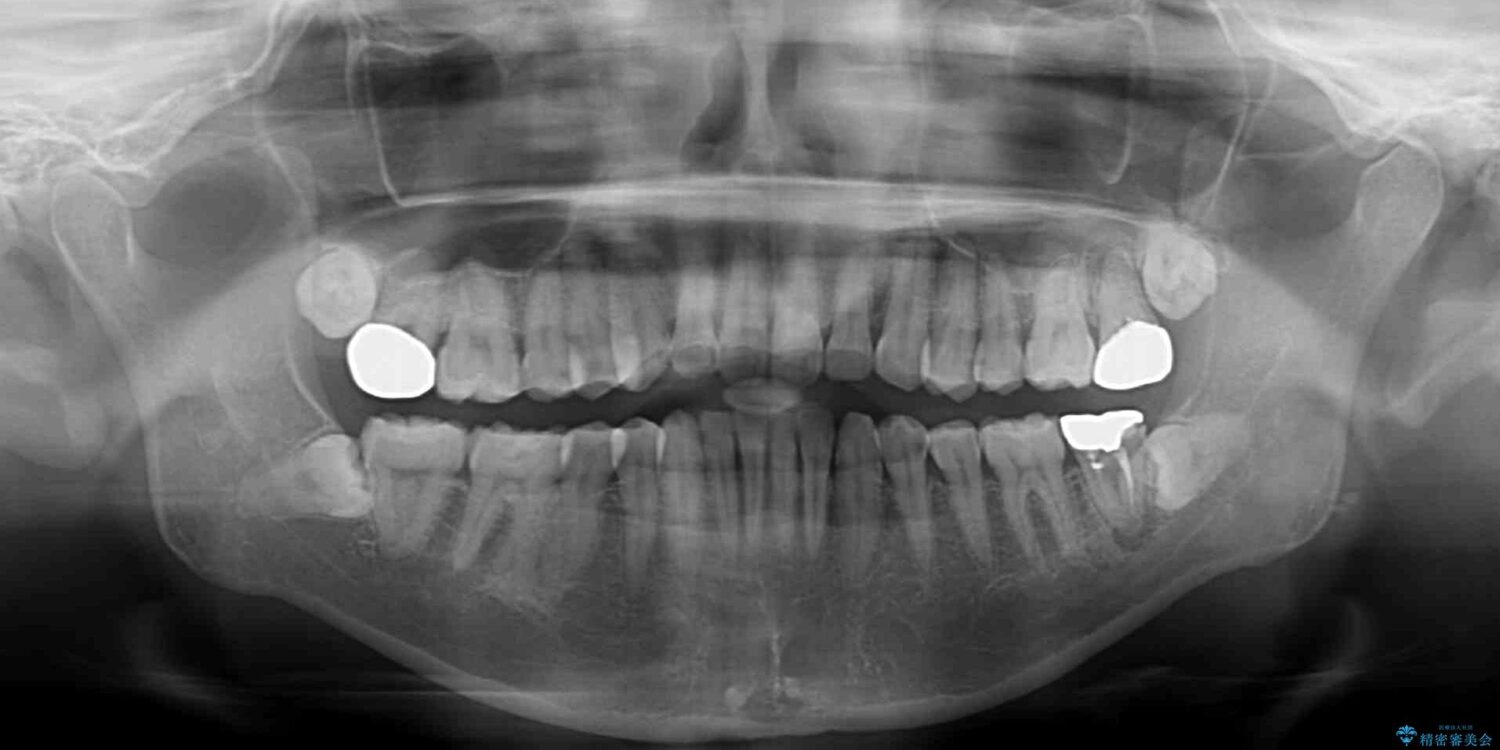

上下前歯や奥歯の虫歯治療を希望して来院された患者様です。

治療計画

全顎的にむし歯が多く、根管治療の必要な奥歯や、審美的に気になっている前歯を中心にオールセラミッククラウンにて補綴治療を行うこととしました。

上顎前歯は歯肉退縮により歯根が露出していたため、事前に歯肉移植術により根面被覆を行い、その後にオールセラミッククラウンを装着することとしました。